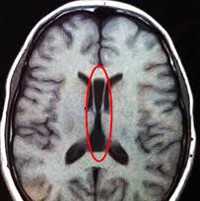

- МРТ головного мозга. Для максимально точной визуализации степени агенезии или гипоплазии мозолистого тела новорожденным выполняется магнитно-резонансная томография в трех плоскостях. По показаниям МРТ может рекомендоваться беременным женщинам для исключения несовместимых с жизнью сочетанных пороков ЦНС.

Случаи с несколькими пороками развития предоставляются для соответствующих генетических исследований, такие состояния при нейрохирургической консультации, обычно требуют нейровизуализации. МРТ позволяет оценить состояние головного мозга. МР-ангиография и флебография используются для описания состояния магистральных сосудов и сагиттального синуса. Для оценки дефектов черепа используется КТ с трехмерной реконструкцией.

В. МРТ незаращенного повреждения врожденной аплазии, зарождение грыжи мозга (перепечатано с разрешения из Child’s Nervous System, Springer-Verlag).